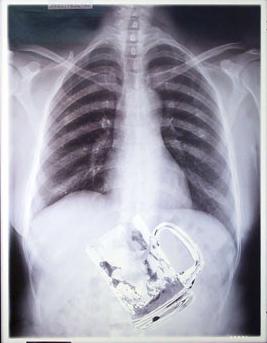

Patient, männl, 56 Jahre, kommt auf die Ambulanz.

Erste Anamnese ergibt folgendes:

gestern abend alkohol zu sich genommen,

kann sich an fast nichts mehr erinnern,

in der Früh thorakale Schmerzen,

Dyspnoe (Atemnot),

später auch starke Schmerzen im Bereich des Abdomens;

Anbei Bild des Thorax-Röngens:

weitere Therapie: operative Entfernung des Fremgegenstands im Ventriculus...